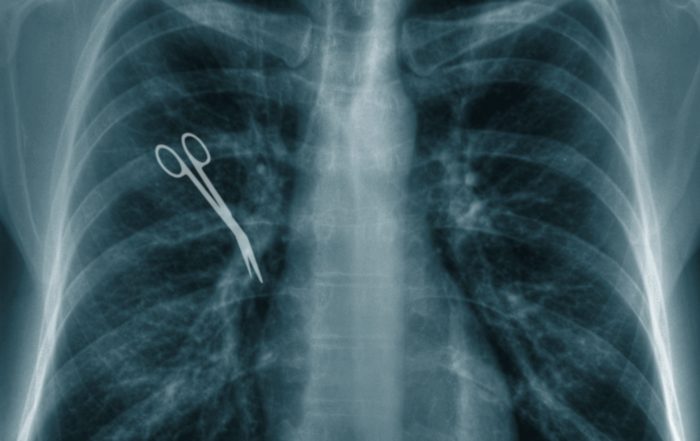

17.500 Euro Schmerzensgeld für vergessenes Bauchtuch - grober Organisationsfehler. Die Patientin bekam 17.500 Euro Schmerzensgeld wegen eines vergessenen Bauchtuchs. Der Operateur (Gynäkologe / Frauenarzt) hat es schlicht versäumt, ein Bauchtuch vor dem [...]